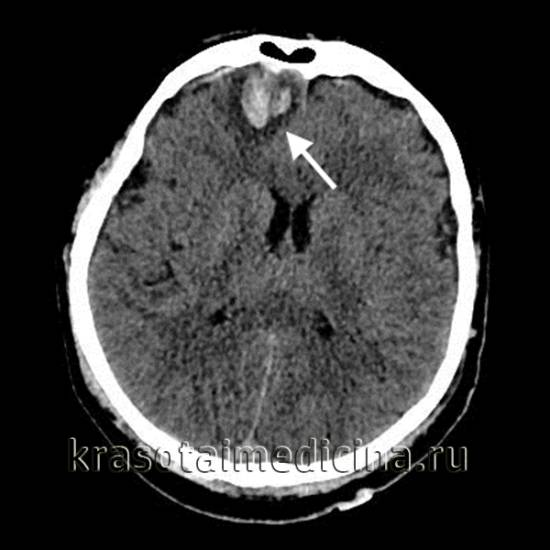

Основным методом диагностики ушибов головного мозга (УГМ) является компьютерная томография (КТ). Томографическая картина зависит от тяжести ушиба. При легкой степени очаги с пониженной плотностью выявляются лишь в 40-50% случаев. В зоне ушиба на томограммах отмечаются отечность и петехиальные кровоизлияния. Отек может охватывать всю долю мозга или даже полушарие, что приводит к умеренному сужению ликворных пространств.

На аксиальной КТ головного мозга без контрастного усиления определяется контузионный очаг в правой лобной доле, представленный геморрагическим компонентом, зоной детрита и отека.

Ушиб средней тяжести характеризуется наличием очагов ушиба в виде зон пониженной плотности. При геморрагическом пропитывании очаг может иметь повышенную плотность. При тяжелом ушибе томография визуализирует очаги как повышенной, так и пониженной плотности: сгустки крови определяются как участки повышенной плотности, а размозжение и отек — как участки пониженной плотности. При крайне тяжелых поражениях зона деструкции церебральной ткани может затрагивать подкорковые структуры.

КТ также проводят в динамике в процессе лечения. Наблюдения показывают, что при легкой или средней тяжести ушиба со временем происходит полное исчезновение очаговых изменений. При тяжелом УГМ наблюдается уменьшение площади очагов деструкции, а затем их трансформация в кисты головного мозга или участки атрофии. Чем тяжелее черепно-мозговая травма, тем медленнее проходят указанные изменения, визуализируемые при помощи КТ.